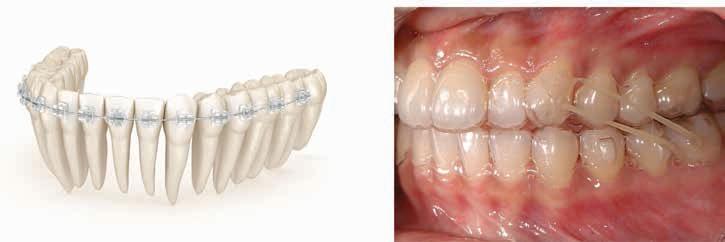

Lichen planus presents in various forms in the mouth including reticular, plaquelike, papular, atrophic, ulcerative, and bullous forms. Lesions range from asymptomatic, white lacy lines (Wickham’s Striae) in the reticular form and dense thickening of the mucosa in the plaque-like form to erythema and ulceration in the atrophic and ulcerative forms. In the former, patients may complain of sensitivity to spicy, acidic, and rough-textured foods as well as difficulty with oral hygiene (Figures 1,2).

Figures 1 and 2. Lichen planus occurring on the gingiva (desquamative gingivitis) and tongue (plaque-like form). Figure 1 Figure 2

A diagnosis based on clinical examination is often acceptable in patients with reticular lichen planus; however, histologic evaluation may be necessary to arrive at definitive diagnoses for the other forms. Direct immunofluorescence may be useful when distinguishing between lichen planus and other oral desquamative diseases.

The cornerstone of treatment of oral dermatologic diseases including lichen planus is the use of high potency topical steroids such as clobetasol and fluocinonide. With severe episodes, tapering doses of systemic steroids are often prescribed as well. Topical steroid therapy can be enhanced by using steroid delivery trays, and intralesional steroid injections may be considered for ulcerative lesions on movable mucosa. Other immune suppressants, both topical and systemic, are used in refractory cases where collaboration with a physician is warranted. Patients often benefit from avoiding products that may irritate the oral tissues including strong flavored toothpaste and mouth rinses as well as spicy, acidic, or rough-textured foods.